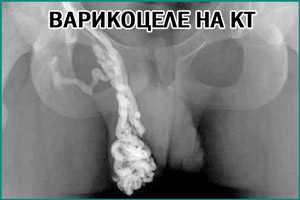

- КТ или МРТ. Они помогают выявить тромбоз сосудов и развитие других патологий, способствующих формированию варикоцеле.